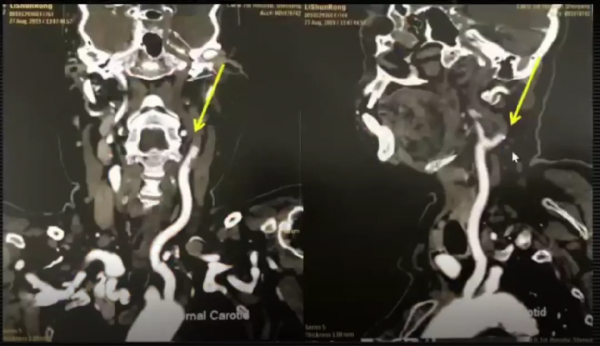

頭頸聯合CTA示左側頸內動脈閉塞(箭頭),左側大腦中動脈閉塞,右側椎動脈部分閉塞,左側大腦後動脈全程未顯影,提示左側大腦後動脈呈完全型胚胎型大腦後動脈。

6、顱腦DWI可見左側大腦半球大面積腦梗死,頭頸聯合CTA提示左側頸內動脈、左側大腦中動脈閉塞,左側大腦後動脈呈完全型胚胎型大腦後動脈。

頭頸部CTA:胚胎型大腦後動脈,頭頸部動脈粥樣硬化改變,左側頸內動脈近端、左側大腦中動脈閉塞,左側大腦後動脈纖細;右側椎動脈顱內段變細;左側頸外動脈近段混合斑塊影,管腔輕中度狹窄。

分析:患者既往存在左側頸內動脈重度狹窄或閉塞,左側大腦後動脈呈完全型胚胎型大腦後動脈(完全由頸內動脈供血),頸內動脈新發的急性血栓形成或栓塞引起了左側頸內動脈及大腦後動脈供血區腦梗死。